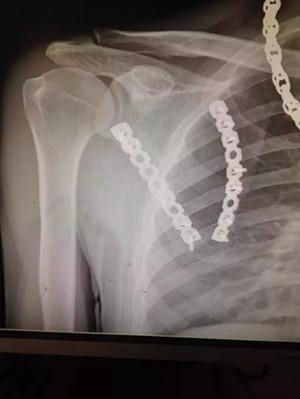

病例一:

患者小吳(化名),因車禍致左膝部受傷到廣安醫(yī)院就診,被診斷為“左脛骨平臺粉碎性骨折”,分屬第Ⅴ型,骨折移位明顯,碎裂嚴重,手術操作難度很大,殘留后遺癥幾率極高。廣安醫(yī)院院長劉志安通過“3D打印”進行“提前干預”,術前對鋼板放置的位置、數(shù)量及確定螺釘?shù)姆较蚝烷L度等,經(jīng)過反復多次的模擬手術,評估不同的手術方法,討論手術策略,制定出最適宜的個性化手術方案。

術后拍片